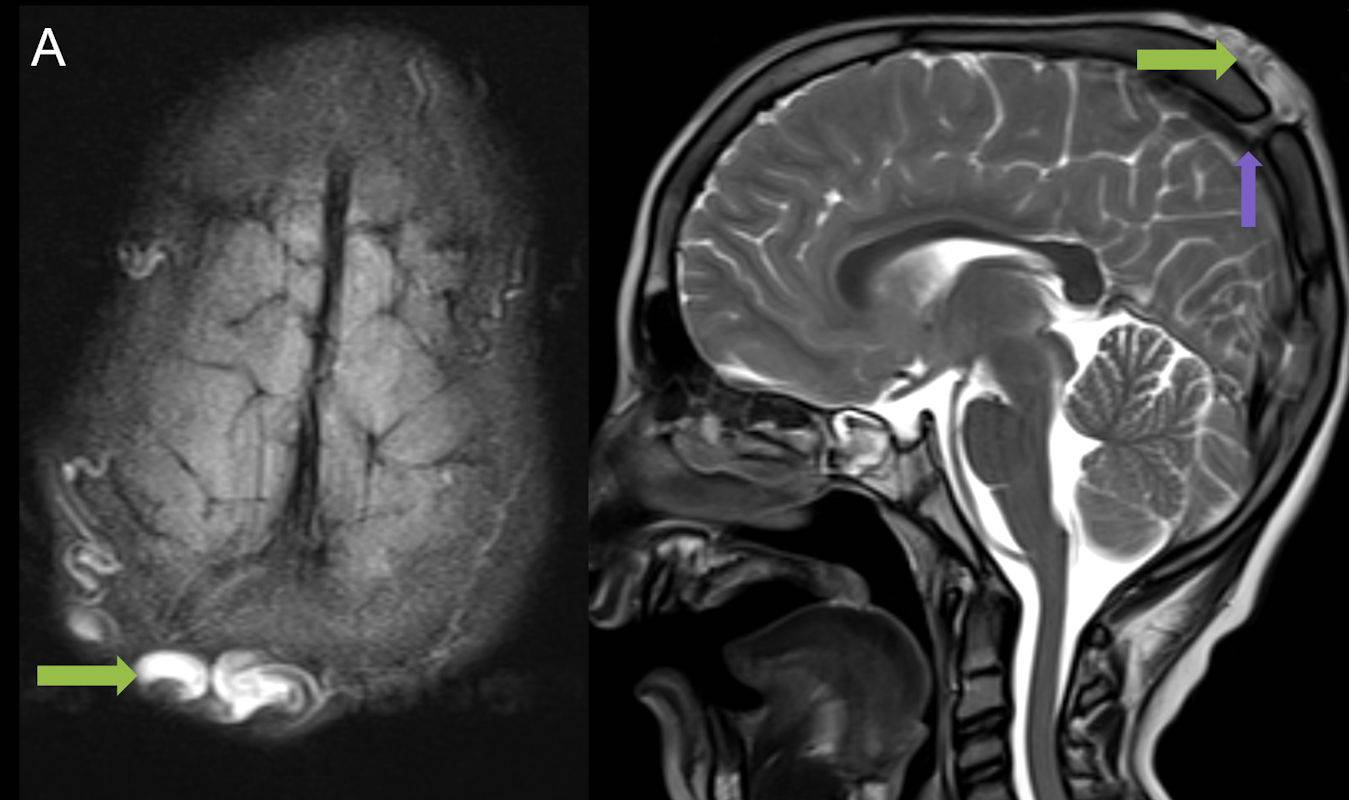

1. A) Kontrastlı FLAIR aksiyel görüntüde ve sagital T2A görüntüde vertekste orta hatta cilt altında dilate tortiyoze vasküler kollateraller (oklar). Paryetal kemikte orta hatta defekt (ok) ve defekt ile ilişkili vasküler yapıların cilt altı yumuşak dokulara uzanımı izlenmektedir.

2. B) Kontrastlı MR venografide orta hatta cilt altı dilate (oklar), tortiyoze emisserian vaskuler yapıların superior sagital sinus ile ilişkisi ve devamlılığı (ok) izlenmektedir.